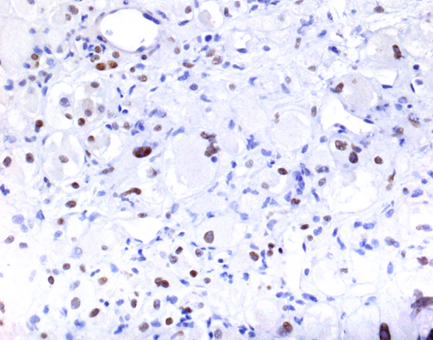

| Figure 3. TFE-3 immunohistochemistry (400X) |

Immunohistochemistry showed that the tumor cells were reactive with antibodies to TFE-3 (Fig 3), HMB-45 (Fig 4), cathepsin K, and MITF. The tumor cells were negative for AE1/3, CAM 5.2, ER, PR, S100, Melan A, arginase 1, INI-1, CD31, E-cadherin, SMA, desmin, and inhibin. The electron microscopy study failed to reveal intracytoplasmic crystals. The FISH assay for rearrangement of TFE-3 locus gene at Xp11.2 was negative.

The immunohistochemical features to distinguish PEComas from other neoplasms is the unique coexpression of both melanocytic and smooth muscle markers. The most important diagnostic criterion, according to WHO classification of tumors, is the presence of HMB-45-positive myoid cells. PEComas with a predominant component of clear cells also show extensive TFE-3 and cathepsin K positivity, but they are not typically associated with tuberous sclerosis complex mutations.

The chief histologic differential diagnosis in our case included metastatic mammary carcinoma, alveolar soft part sarcoma and malignant melanoma. Review of the previous mastectomy, the negative immunohistochemistry for breast markers and the unusual morphology largely ruled out a metastatic breast carcinoma. The organoid growth pattern with loosely cohesive epithelioid cells raised the possibility of alveolar soft part sarcoma. This, however, was excluded by electron microscopy and the lack of TFE-3 gene Xp11 rearrangement. Lack of malignant features such as frequent mitotic figures and necrosis helped excluded metastatic malignant melanoma. Currently, the only curative option for liver PEComa is surgical excision with wide margins. Adjuvant therapy has no defined role in the treatment of metastatic disease. Rapamycin, an inhibitor of mTOR pathway, may be beneficial for patients with metastatic disease.